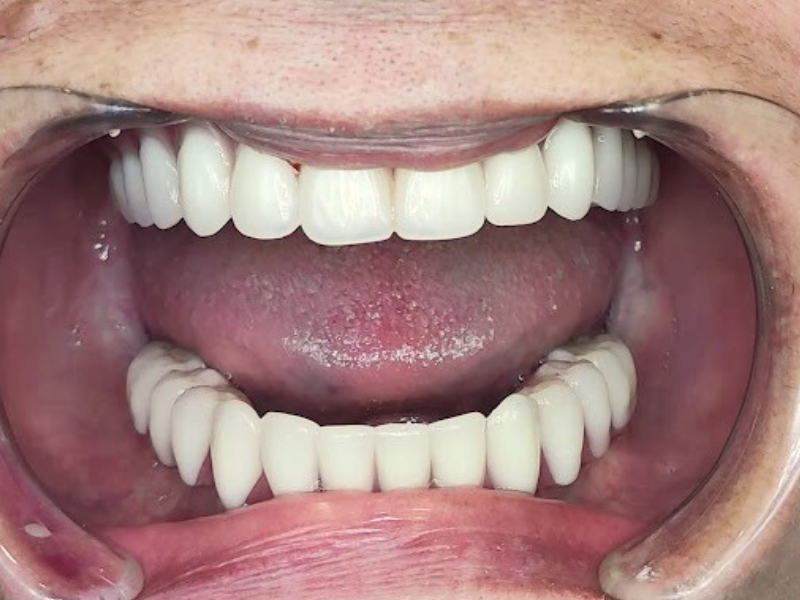

ksenia-all-on-4-all-on-6-after

A smile after the procedure